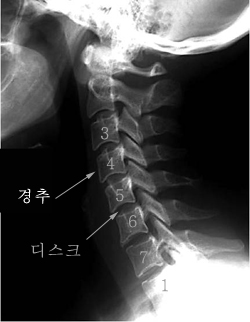

목디스크는 목 쪽 척추인 경추와 경추 사이에 위치한 추간판 사이로 내부의 수핵이 빠져나와서 신경근 또는 척수를 누르는 질환이며 목디스크의 정확한 명칭은 경추 추간판 탈출증이라고 합니다. 잦은 휴대폰 사용과 함께 업무를 볼 때 자연스럽게 구부정한 자세로 앉아 있다 보니 이로 인해 목디스크 증상까지 동반되는 경우가 많다고 합니다. 목디스크는 오랜 시간 축척된 경추 관절 및 디스크의 퇴행성 변화가 원인입니다.

통증이 팔, 어깨, 팔에서 손 및 손가락 등으로 뻗치게 되는데 이때 신경 분포에 따라서 대개 5번 신경이 눌리면서 어깨가 아프고, 6번 신경이 눌리게 됩니다. 또한 어깨에서부터 팔을 지나 엄지손가락까지 저리고 아프게 되면서 7번과 8번 신경이 눌려지게 되어 손과 손가락 마디마디까지 힘이 빠지게 될 수 있습니다.